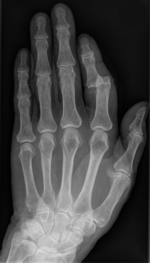

| − | |Bilder=[[Datei:.jpg|thumb| | + | |Bilder=[[Datei:Ausgerenkter_Zeigefinger.jpg|thumb|150px|center|Ausgerenkter Zeigefinger]]}} |

In den verschiedenen Sportarten ist das Verletzungsrisiko unterschiedlich hoch. Auch die auftretenden Verletzungsarten sind unterschiedlich.

So spielt zB beim Schifahren die hohe Geschwindigkeit, oder bei den verschiedenen Ball-Mannschaftssportarten das hohe Zweikampfrisiko eine wesentliche Rolle.

Bei den meisten Verletzungen im Sport sind: Haut, Muskulatur, Sehnen, Bänder, Knochen oder der Kopf betroffen.